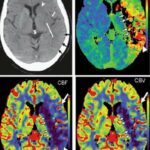

- 뇌 구조 및 기능 이상: 뇌의 특정 부위에서 발생하는 비정상적인 전기 활동이 결여발작을 유발할 수 있습니다.